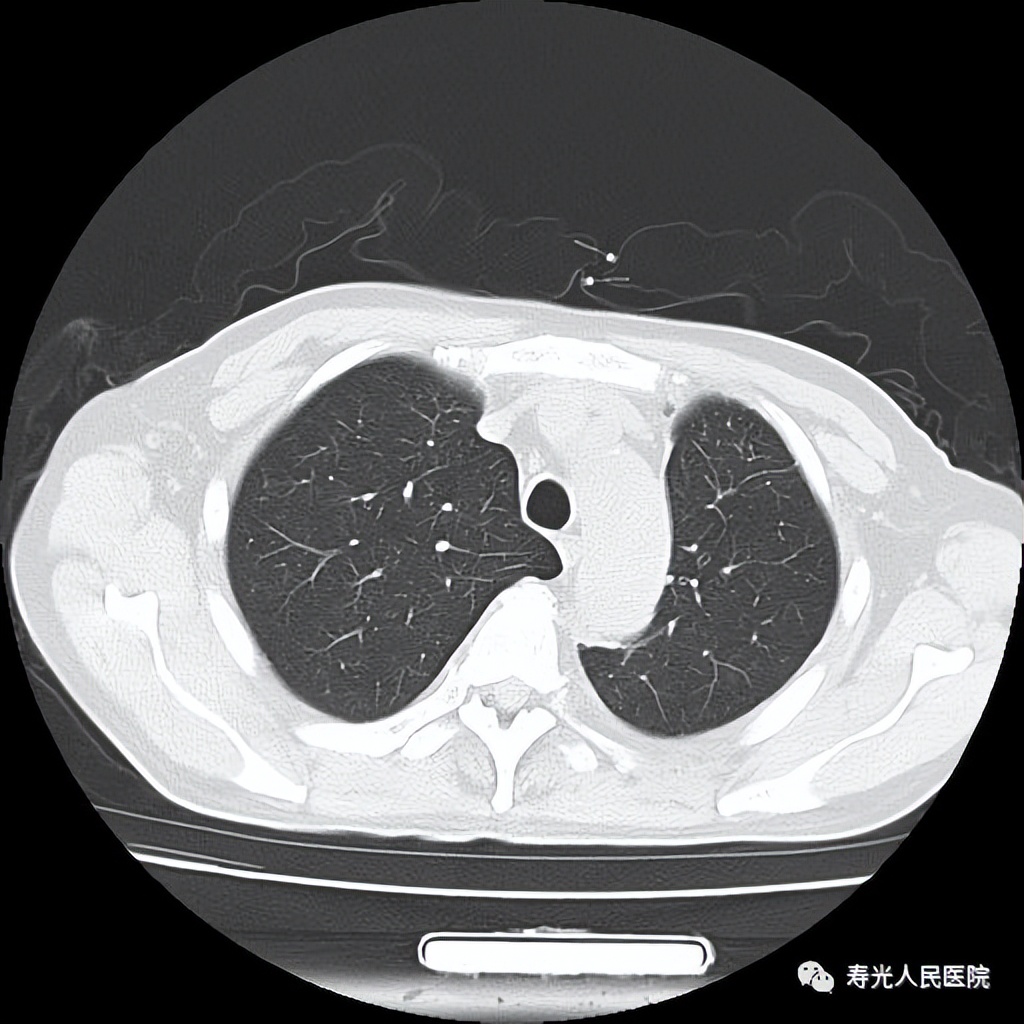

该患者,脑外伤加多器官损伤,合并重度肺实变,病情重,手术难度大,在科室全体医护人员的共同努力下,左侧肺实变及胸部损伤得以快速、成功救治,术后恢复良好,挽救了患者及其家庭,治疗效果满意。患者于2022年12月20日顺利出院,于2023年1月7日再次复查胸部CT,提示左侧肺恢复好,于2023年2月电话随访患者,已恢复基本劳动。

出院时,复查胸部CT,恢复正常